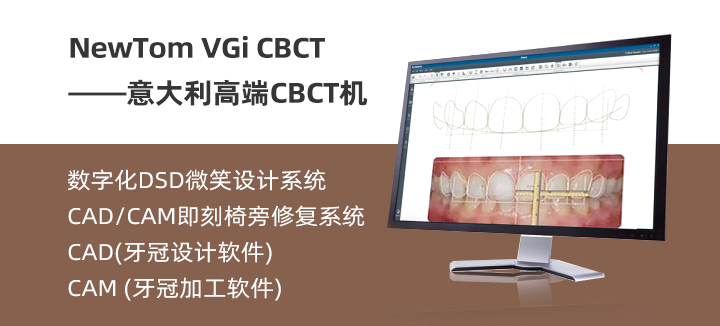

运用CBCT技术、数字化软件技术、CAD/CAM技术,即计算机辅助设计和计算机辅助制造技术,机器人导航技术以及数字化材料技术。同时兼顾口腔美学理念,基于“黄金分割比例”等美学标准,对牙齿色泽、质感、宽度比例、微笑曲线进行准确分析与设计,一次性完成全瓷修复体、全冠和贴面的光学取模、设计、研磨、试戴、安装等全部程序。整个过程需要的时间比较短,只需一次就诊,真正实现立等可戴,让牙齿效果更理想、更美观、更省时。